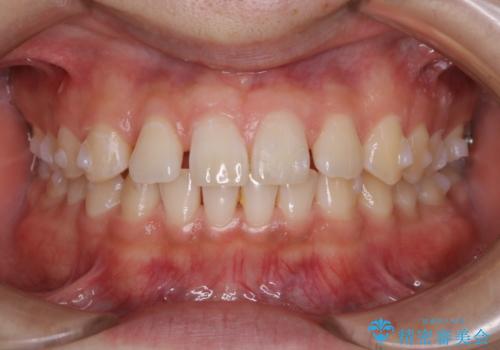

- 上のすきっ歯が気になるとご相談にいらした方です。上下顎ともにスペースがあったため、インビザラインFULLにて見た目と噛み合わせの改善も同時に行いました。

元々は上前歯のみの部分矯正をご希望されていましたが、下の歯もスペースがあり、噛み合わせ的にも上のみの部分治療は難しいことをお話ししました。前歯のみの部分矯正を行った場合、前歯の隙間だけが閉じて奥歯が噛めなくなってしまう場合もあります。インビザラインFULLにて治療することで、噛み合わせと見た目を同時に改善させることができ、大変喜んでいただけました。